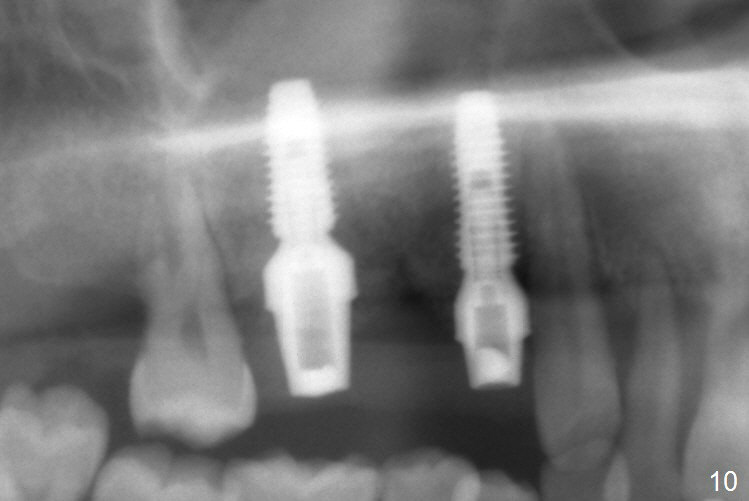

The 36-year-old man (ex-smoker, quit for 4-5 years) insists upon #3 and 5 extraction first for implants, in spite of more severe infection at #7, 14,19,30 (Fig.1-4). The gingiva around #23-26 implants is healthy 3 weeks postop (Fig.5). The initial depths at #3 and 5 are 8.5 mm (bone-level) and 18 mmm (gingiva-level (13 mm (implant length) + 5 mm cuff), respectively. When a drill penetrates the sinus floor, confirm the depth. After use of 3.8 mm drill, 4.5 mm tap drill is inserted at #3 without stability, while a 4.5x13 mm implant is placed at #5 with primary stability (Fig.6,7). Then a 5x11.5 mm is placed at #3 subcrestal proximally after sinus lift with Vanilla graft (without sinus membrane perforation; Fig.8). The implant at #5 is seated ~1 mm deeper (subcrestal mesially (^^); supracrestal distally (^)); allograft is placed around the implants prior to insertion of 6.5x7(5) and 5.5x4(5) mm abutments; last more allograft is added (Fig.9 *, 10). The implants seem to have been osteointegrated 4.5 months postop (Fig.11,12). The gingiva is healthy around the implants without bone loss 3 months post cementation (Fig.13,14).